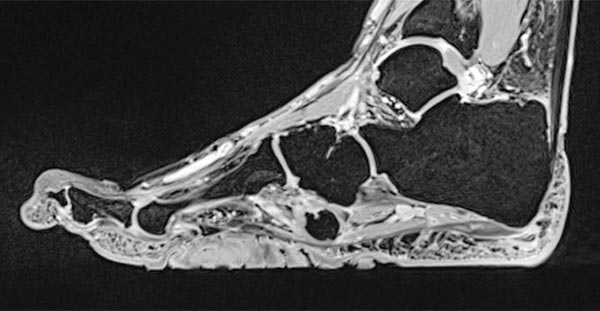

Preoperative imaging of the cerebriform mixed connective tissue nevus in MRI, here sagittal T2-weighted, fat-suppressed sequence of the right foot. The connective tissue nevus is homogeneously hypointense (black) due to the high fibrotic content.